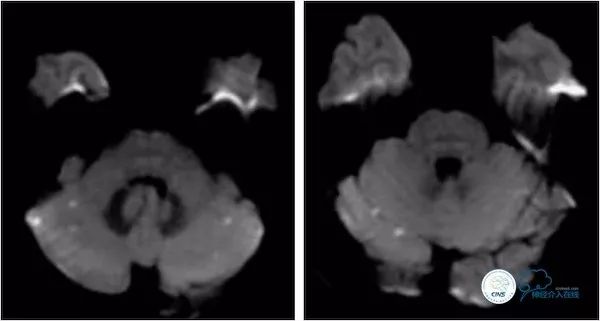

患者,男,69岁,主因“基底动脉球囊扩张术后1.5年,发作性头晕2月”入院。患者1年9个月前(2016-2)出现发作性头晕,持续数分钟后缓解,反复发作后遗留头昏沉感及走路不稳伴行走右偏,就诊附近医院,MRI示双侧小脑半球多发栓塞(图1)。

图1